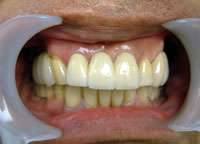

治療完了

平成19年5月1日

(治療期間:2年10ヶ月)

平成21年1月29日

(治療期間:1年7ヶ月)

57歳 女性

インプラント21本 すべてジルコニア冠